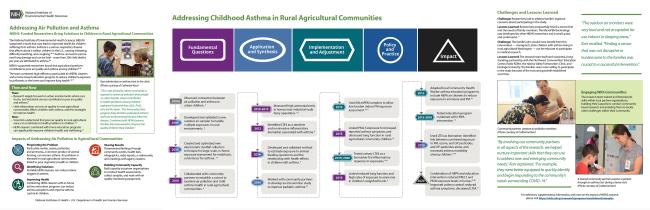

Discoveries emerging from NIH-supported research have led to new ways to prevent, diagnose, and treat illness, ultimately improving the health of the nation and the world.